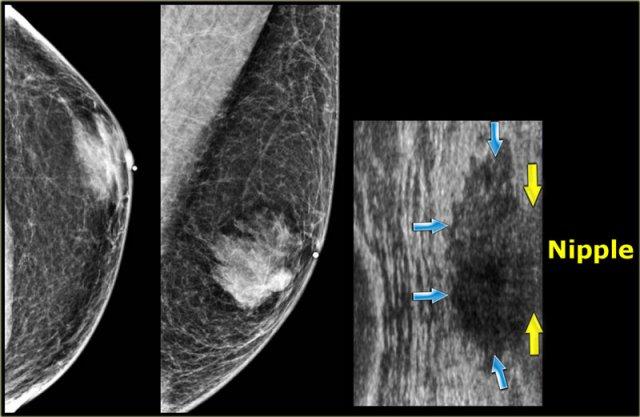

Bên trái là nhũ ảnh và hình siêu âm của một bệnh nhân có gynecomastia thể nốt tuyến.

Lưu ý tổn thương nằm ngay dưới núm vú.

Hình siêu âm cho thấy hình ảnh điển hình của gynecomastia: một khối giảm âm với bờ thùy múi hoặc thậm chí có gai.

Nếu đây là hình ảnh của một phụ nữ, bạn sẽ nhận định đây là một khối có vi thùy múi và gai, tức là Birads IV hoặc V.

Ở nam giới, đây là hình ảnh điển hình của gynecomastia.

Bên trái là cùng hình siêu âm đó, nhưng ở tư thế bình thường.

Lưu ý hình ảnh trông ‘ác tính’ như thế nào.